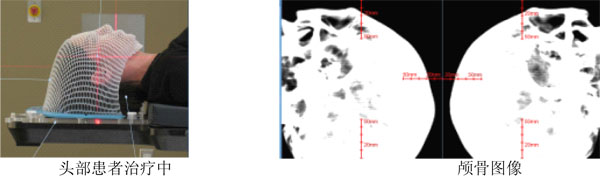

一、6D颅骨追踪

颅骨追踪是基于刚性结构的配准,是以骨性标记作为追踪的参考。实时获得X线影像与重建的DRR影像进行比较,计算机计算出颅骨位置的6维偏差,治疗床和机械臂自动调整位置,修正平移和转动偏差。其特点是刚性配准精度高,而且无创,颠覆了传统的使用颅骨钉固定的方式实现精确放疗。